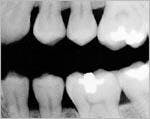

Recently, a patient came in to see me for a routine checkup. He reported some occasional pain in his lower left quadrant. In Figure 1, you will see a reproduction of the digital bitewing that we took in my office that day.

We noticed a vertical line running from the bottom of his amalgam restoration down to the pulp chamber. When we enhanced the image using the Clear-Vu tool in our DEXIS digital radiography system (see Figure 2), the fracture was clearly evident. We then took a conventional X-ray film, shot at regular speed and hand-developed at 68 degrees. By contrast, the vertical line was not evident on that film at all!